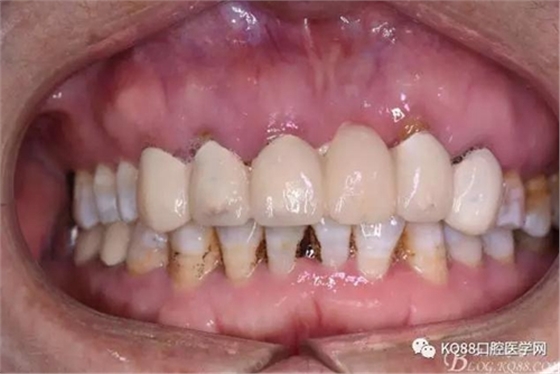

圖3.術(shù)前口內(nèi)正面照:12前庭溝輕度捫痛、有乒乓感